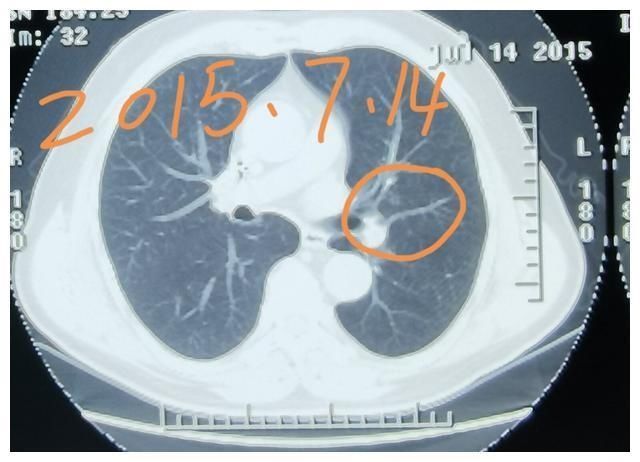

这是一位男性患者,在六年前体检,发现了左肺上叶有一个8毫米的磨玻璃结节,比较浅淡,通过了六年的观察,这个结节现在最大径长到了11毫米,这位患者今年快80岁了。这个肺结节不能除外有早早期肺癌或者癌前病变的可能性,患者身体状态不太好,有一些心脏方面的合并症,并且这个结节位置比较深,可以继续再观察。给大家放了是六年前的片子,去年以及今年的片子,中间有三年的片子没有放,因为和两年前差不多。

【 肺磨|刘懿博士说肺癌(三〇一五)6年长3mm,肺磨玻璃结节长得快还】肺磨玻璃结节型肺癌被称为惰性生长的癌症,有的人称之为懒癌,发展的不是很快。如果这个磨玻璃结节在短期内突然间长得很大,那基本可以排除肺癌,因为肺癌不会长那么快。